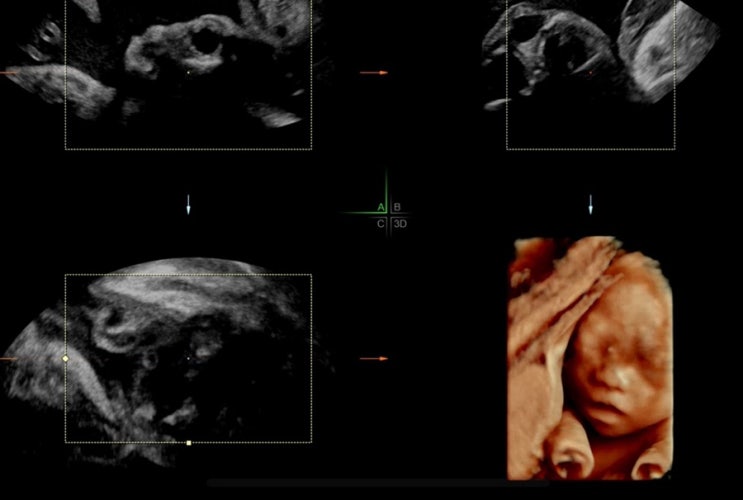

[임신 34주차] 동탄제일병원 막달검사 (34주 2kg) | 제로이드 인텐시브 MD 실비 (삼성화재) | 산모신생아 건강관리서비스 신청 (복지로)

#동탄제일병원_막달검사 는 34-36주 사이에 진행한다 원래 35주에 예약 잡아놨었는데 32주에 선홍빛피비침...